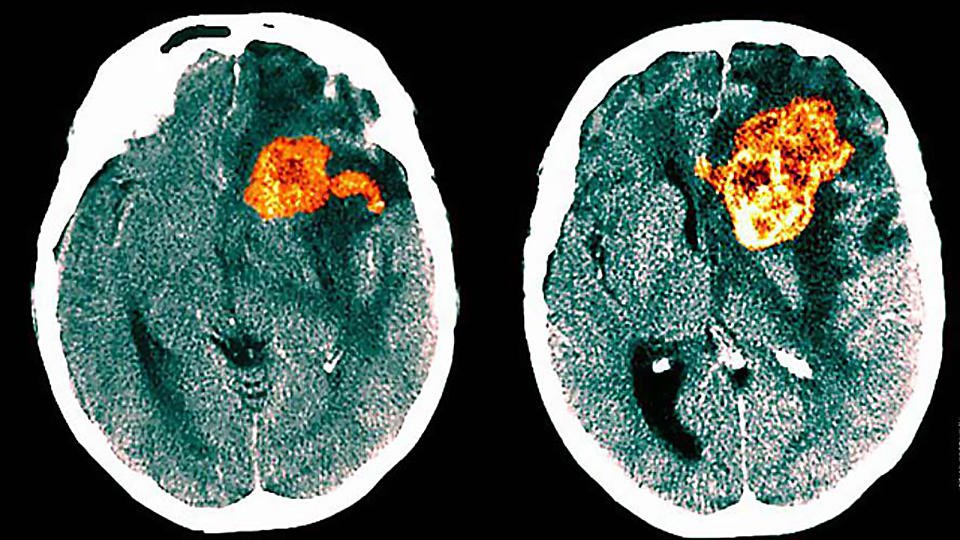

Создан препарат против смертельной глиобластомы

Ученые из Канады создали препарат, который способен помочь против смертельной опухоли мозга - глиобластомы. Лекарство создано на основе CART-клеточной терапии.

Почти во всех случаях после агрессивного лечения глиобластома рецидивирует в более агрессивной форме уже через семь месяцев, чем она и опасна, сообщает Cell Stem Cell.

При T-клеточной терапии используется специальный антигенный рецептор, который распознает злокачественные клетки и уничтожает их. Это белок с фрагментами антитела, который избирательно связывается с определенными антигенами.

Кроме того, в лечении задействованы и T-клетки пациента, которые определенным образом модифицируют.

Эксперименты на мышах показали, что клеточная терапия повышает выживаемость пациентов и снижает опухолевую нагрузку.